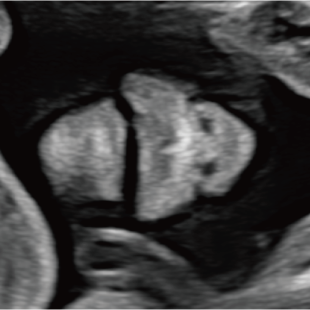

妊娠中期になると、胎児の体や内臓の構造がよりはっきりと確認できるようになります。 中期スクリーニングでは、頭部、顔面、頸部、胸部、腹部、心臓、手足、外性器、臍帯や胎盤など、全身をくまなく観察し、形態の状態を詳しく確認します。この頃に染色体数の変化を疑わせる所見が確認される事もあります。

胎児ドックの様子_中期_頭 胎児ドックの様子_中期_顔面 胎児ドックの様子_中期_心臓 胎児ドックの様子_中期_腹部 胎児ドックの様子_中期_足 胎児ドックの様子_中期_4D

妊娠後期は、胎児の成長がさらに進み、発育の途中で現れてくる変化を確認できる時期です。中期の検査では問題が見られなかった場合でも、成長に伴って形態の変化が現れることがあります。また、構造だけではなく、胎児機能(赤ちゃんの元気度)の評価も可能となります。後期スクリーニングでは、各臓器の状態や構造に加え心臓の動きや血液の流れなどをより詳しく観察します。

胎児ドックの様子_後期_頭 胎児ドックの様子_後期_心臓 胎児ドックの様子_後期_心臓 胎児ドックの様子_後期_足 胎児ドックの様子_後期_4D